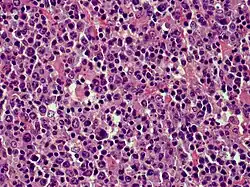

Cutaneous B-cell lymphoma

| Cutaneous diffuse large B-cell lymphoma | |

Cutaneous B-cell lymphomas (CBCL), more recently termed Primary cutaneous B-cell lymphomas and lymphoproliferative disorders (PCBCLPD), are a group of disorders that typically present as skin lesions consisting of proliferating B-cells. B-cells are a type of lymphocyte involved in regulating immune responses. (The "primary" used to designate cutaneous lymphomas indicates that the lymphoma was first diagnosed as limited to the skin and there was no evidence of spread to extracutaneous tissues for 6 months after the diagnosis was first made.[1]) Since its original definition in 1997, CBCL has been considered to have a varying number of subtypes by the European Organisation for Research and Treatment of Cancer, i.e., EORTC, and World Health Organization, i.e., WHO.[2] The latest revised classification of CBCL, which was published by EORTC in 2022, lists the following three main subtypes of CBCL (now termed PCBCLPD):[3]

- Primary cutaneous marginal zone lymphoproliferative disorder (formerly termed primary cutaneous marginal zone lymphoma)

- Primary cutaneous follicular lymphoma (also termed primary cutaneous follicular center lymphoma or primary cutaneous follicular centre lymphoma)

- Primary cutaneous diffuse large B-cell lymphoma, leg type

Because recent studies had shown that primary cutaneous marginal zone lymphoma, which was formerly classified as a subtype of the MALT lymphomas: a) has a distinct microscopic histology and gene expression profile; b) spreads to extracutaneous tissue in only 4 to 8.5% of cases; c) has a 5 year disease-specific survival in excess of 99% even in patients not receiving aggressive therapy; and d) has pathological findings that overlap the benign cutaneous disorders termed cutaneous lymphoid hyperplasia. Consequently, EORTC, 2022, renamed primary cutaneous marginal zone lymphoma as primary cutaneous marginal zone lymphoproliferative disorder.[3] Primary cutaneous follicle center lymphoma is also an indolent lymphoma.[4] The majority of patients achieve complete remissions following surgery and/or radiation therapy. Its spread to extracutaneous tissues is rare (10%) and has a 5-year overall survival and disease-specific survival of 87% and 95%, respectively.[3] Primary cutaneous diffuse large B-cell lymphoma, leg type is an aggressive B-cell lymphoma that is often resistant to therapy and carries a poor prognosis,[5] i.e., they have a 5-year disease-specific survival rate of 43% or 70% depending on whether their cancer cells have or do not have, respectively, inactivating mutations in both of their CDKN2A genes.[6]